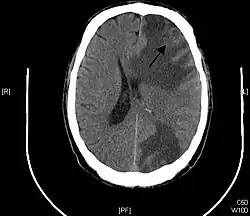

Las localizaciones más frecuentes de las metástasis son los órganos más irrigados por la sangre como son el cerebro, los pulmones, el hígado, los huesos y las glándulas suprarrenales. La excepción a esta regla son los riñones y el propio corazón, pese a que por sus cavidades pasan muchos litros de sangre al día.